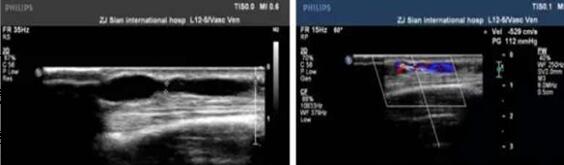

患者为通海县一名维持性血液透析患者,自体动静脉内瘘术后一年,近期透析时内瘘血管血流量明显不足(<200ml/min),故转诊我院肾内科。经CT血管造影术(CTA)检查发现左上肢动静脉内瘘血管头静脉段重度狭窄。术前经副主任孙阳及科室血管通路小组医护团队评估讨论,积极与B超室周宏伟主任沟通,于6月20日在B超引导下顺利进行了“内瘘血管狭窄球囊扩张成型术(PTA)”。该手术由周宏伟主任负责B超引导,肾内科卢永新主治医师负责操作,手术耗时一小时,内瘘血管狭窄段在球囊扩张下逐渐复张,术后B超评估显示狭窄段血管扩张良好,查体内瘘血管杂音及震颤明显增强,术后第二天使用内瘘血管行血透治疗,血流量达230ml/min以上,使用效果满意。

术前